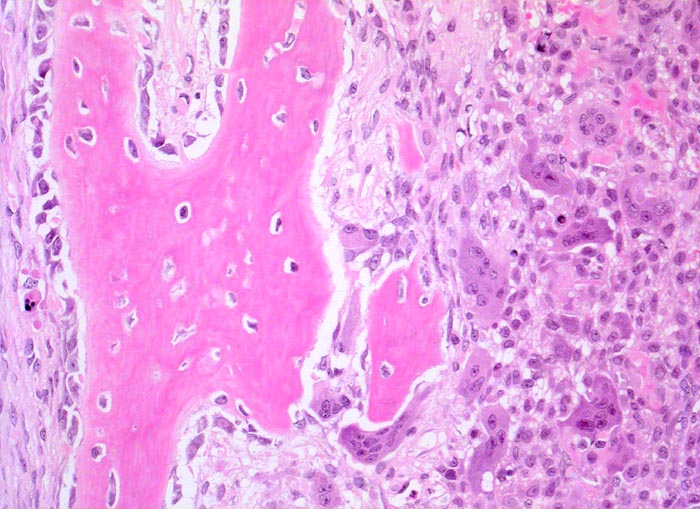

Die AKZ ist charakterisiert durch kavernöse Bluthohlräume mit dazwischengelegenen zellreichen Septen unter Einschluss von Riesenzellen. Da sekundäre AKZ häufig sind, muss das gesamte Material histologisch untersucht werden.

• Pseudozystische kavernöse Bluthohlräume eingebettet in Skelettmuskulatur.

• Die bindegewebigen Pseudozystenwände enthalten solide Massen von mononukleären histiozytenartigen Zellen mit eingestreuten mehrkernigen osteoklastären Riesenzellen.

• Neugebildeter reaktiver Faserknochen mit Osteoblastensaum in der Peripherie der Hohlräume.